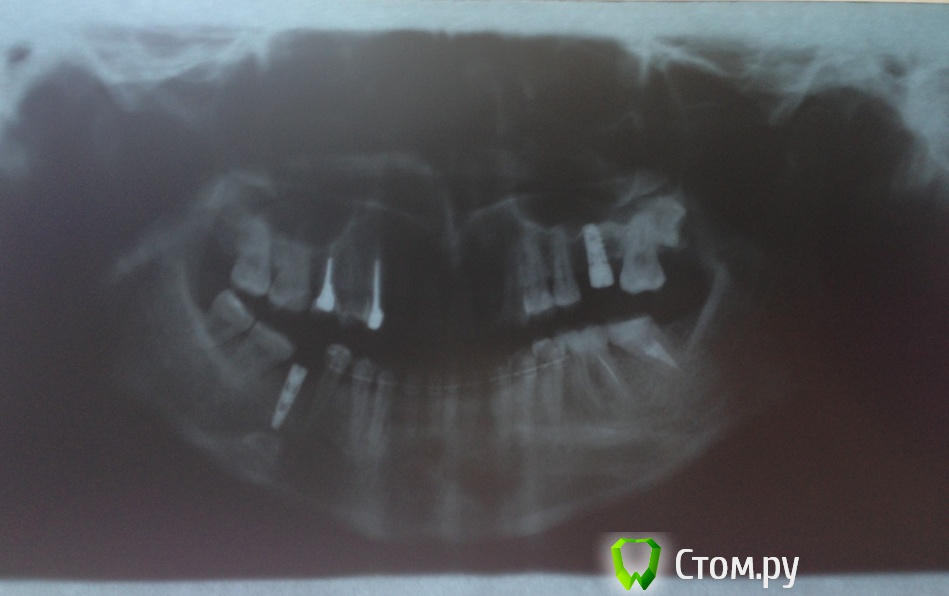

Nnn Опубликовано 23 апреля, 2014 Автор Поделиться Опубликовано 23 апреля, 2014 (изменено) На всякий случай снимки. Я писала про один имплант в своем вопросе, но на самом деле у меня два импланта, еще вверху один тоже на корневом зубе. Там тот же вопрос с коронкой Изменено 23 апреля, 2014 пользователем Nnn Ссылка на комментарий